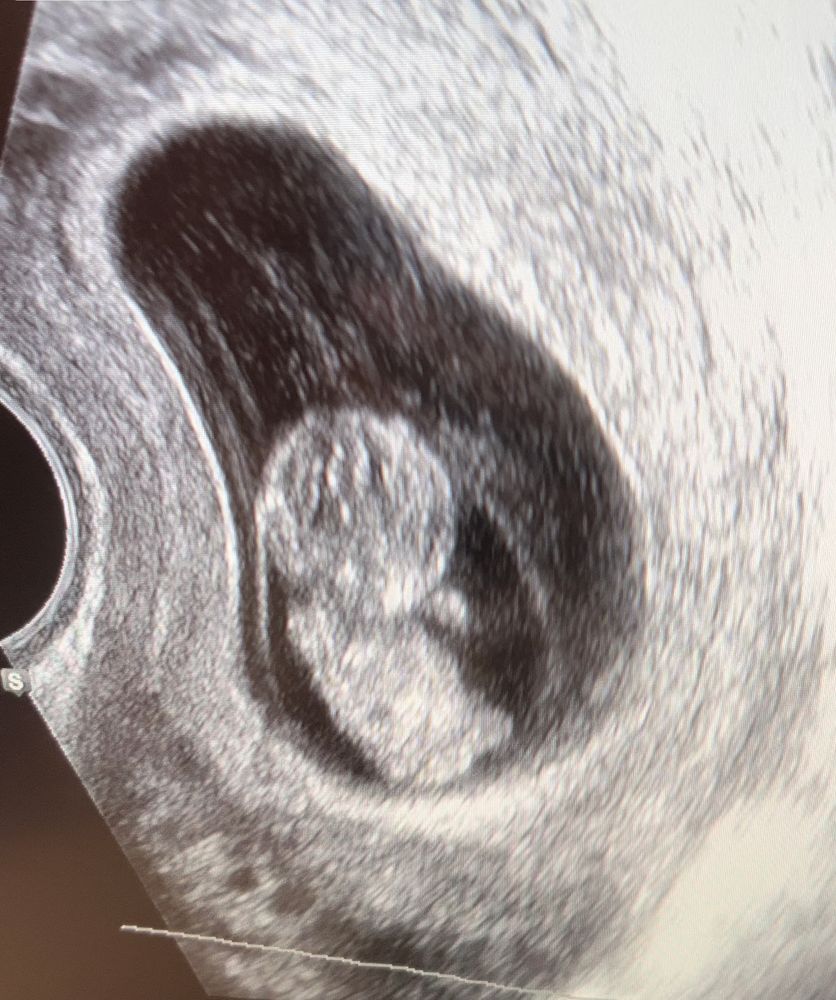

9 недель и три дня

Мы с Вами рядышком) Вчера тоже была на узи, 10.0 срок) 3 см уже😍 крутился вертелся уже, так активно двигался, я смотрела и не верила, что это со мной происходит🥰 и так ещё необычно, что он внутри уже шевелится, а ничего не чувствуешь и живота ещё нет) только токсикоз каждый день напоминает, что всё в порядке😂 сдала ещё нипт, теперь жду результатов с нетерпением! И на скрининг 22.08.!

Такая милота! В 9 недель ни разу не ходила! Как-то был или по меньше, рыбкой ещё без ручек, без ножек. Или уже такой конкретный, большой. А тут кроха-лапусик такой! Расти здоровеньким и радуй маму! 🤗

Они такие славные получаются на фотографиях на этом сроке) Правильный подход к проходу врачей, и без нервов и суеты. Берегите себя) Лёгкой беременности!🌷